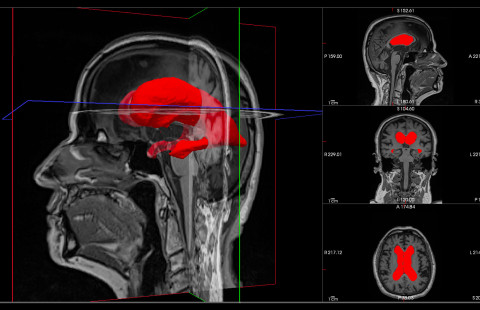

The ACCESS-AD consortium brings together 30 organizations. The initial budget is over 37 million euros.

A recent study establishes a direct analytical link between the axonal microgeometry and non-invasive, millimetre-scale diffusion MRI signals.